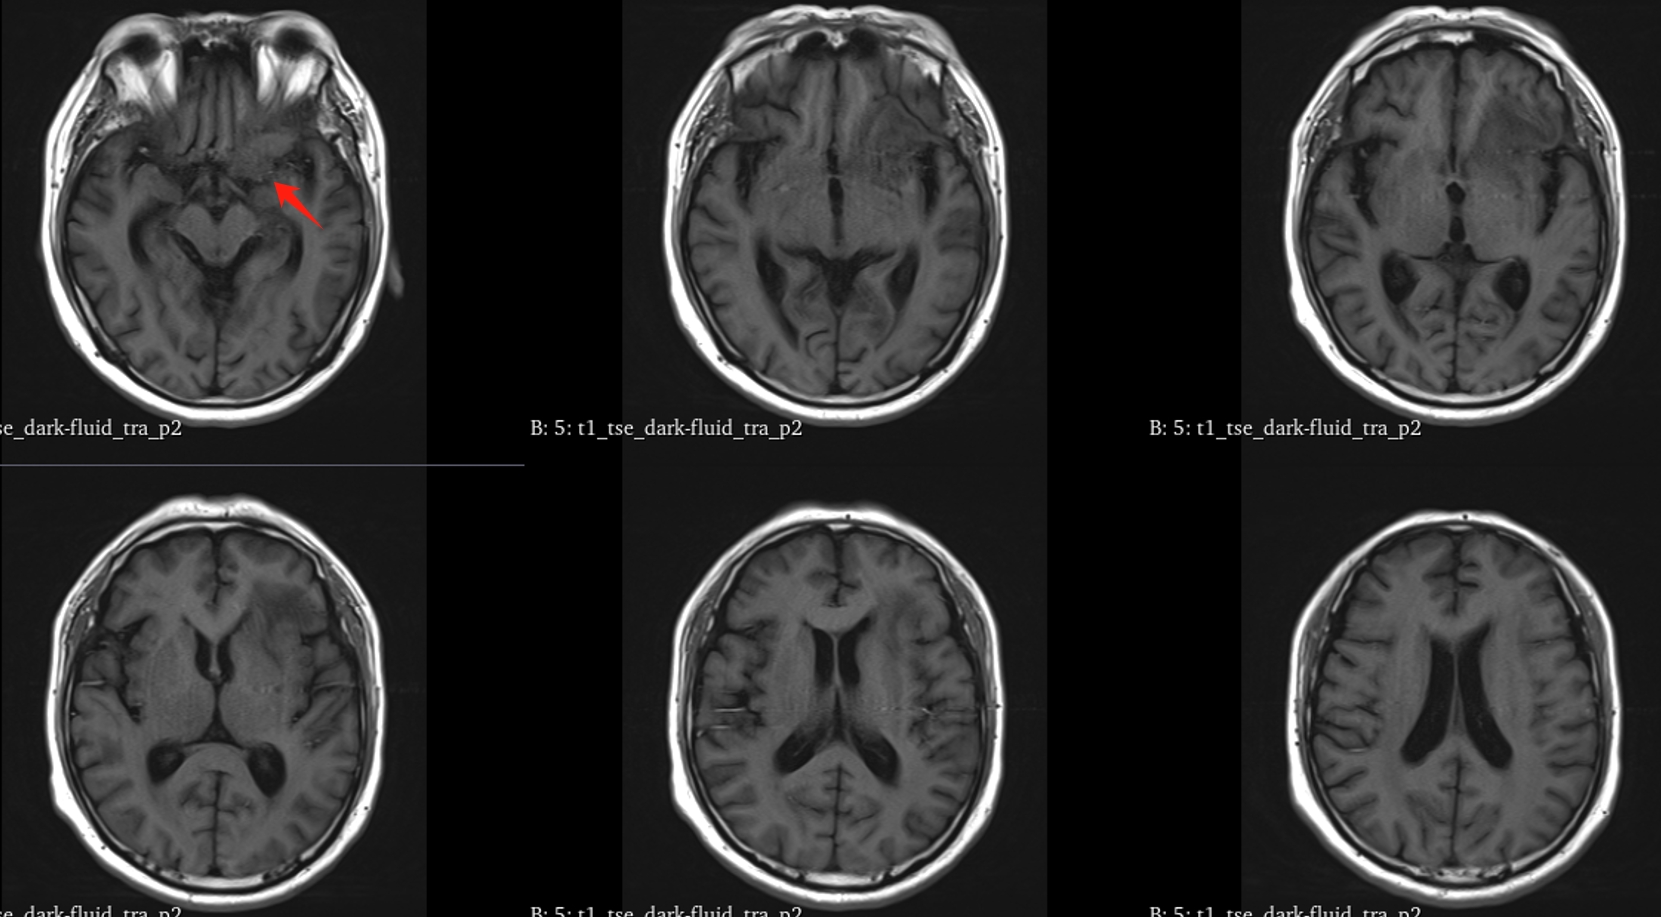

该患者入院后完善常规颅脑影像学检查,左侧颞叶病变,疾病性质不详,转移瘤、胶质瘤、炎症类疾病均不能排除,遂行PET-CT检查,提示左侧颞叶高代谢,淋巴瘤不能排除。组织MDT会诊建议可先行腰椎穿刺查脑脊液脱落细胞学、感染指标,若仍不能确诊,可进一步行开颅病灶切除,术中快速冰冻,根据冰冻结果决定手术手术策略。患者脑脊液脱落细胞学结果:较多淋巴细胞,少许单核细胞及个别中性粒细胞,未见异形细胞,脑脊液常规、生化、脑脊液培养未见细菌生长,诊断仍不能明确,且患者病情进展迅速,患者神志呈昏睡状态,颅脑MRI提示病变较前明显增大(影像学检查间隔两周),且水肿明显加重,遂行开颅病变切除术。术中见部分病变累及蝶骨嵴硬膜,病变质地硬韧,内有多个囊腔,囊内容物为黄色粘稠样脓性物质,留取囊液及实性部分送快速冰冻,在等待冰冻过程中,进一步探查见肿瘤侵犯左侧颞叶,该部位肿瘤质地相对软,无包膜,与周围脑组织无边界,血运不丰富,内有多个囊腔,且肿瘤侵犯侧裂池、颈动脉池,左侧视神经、颈内动脉、大脑中动脉均被病变包绕,且该处肿瘤质地偏硬韧。术中快速冰冻提示组织大片变性坏死,伴胶质增生及淋巴增生。结合病变质地及冰冻结果,考虑为非肿瘤性疾病,可能为炎性病变伴肉芽肿形成可能性大,且肿瘤质地硬韧,累及范围广泛,难以全切,遂行肿瘤大部分切除后结束手术。术后病理结果明确后予以伏立康唑、醋酸卡泊芬净抗真菌治疗。在治疗过程中患者先后出现脑出血、脑梗塞,最终因治疗周期长,花费高、效果不确定等因素,家属放弃治疗,于术后1月去世。

GM实验,GM是曲霉菌细胞壁的主要成分,是疾病早期释放至体液中的抗原之一。据报道,脑脊液GM试验诊断ICA的敏感度及特异度分别为88.2%及96.3%,且阳性预测值及阴性预测值均超过90%,脑脊液GM水平与曲霉菌感染严重程度相关,监测该指标可评价治疗效果及预后。影像学检查具有多样性,多为反复慢性炎症、肉芽肿样改变,部分易累及颅底。

目前确诊ICA仍依赖于病灶切除或活检,获得组织病理学、直接镜检或培养证据。《颅内曲霉菌病诊治中国专家共识》推荐:当临床症状怀疑ICA时,应尽早行脑脊液检查(常规、生化、培养、G试验、GM试验及mNGS)及颅脑MRI平扫+增强检查。怀疑窦源性ICA时,还应加做颅底CT检查。当临床症状符合ICA,但上述检查结果为阴性时,可重复送检。条件允许时,及时行标本镜检与培养获得确切证据。尤其是对于长期应用激素、免疫功能缺陷高危患者。